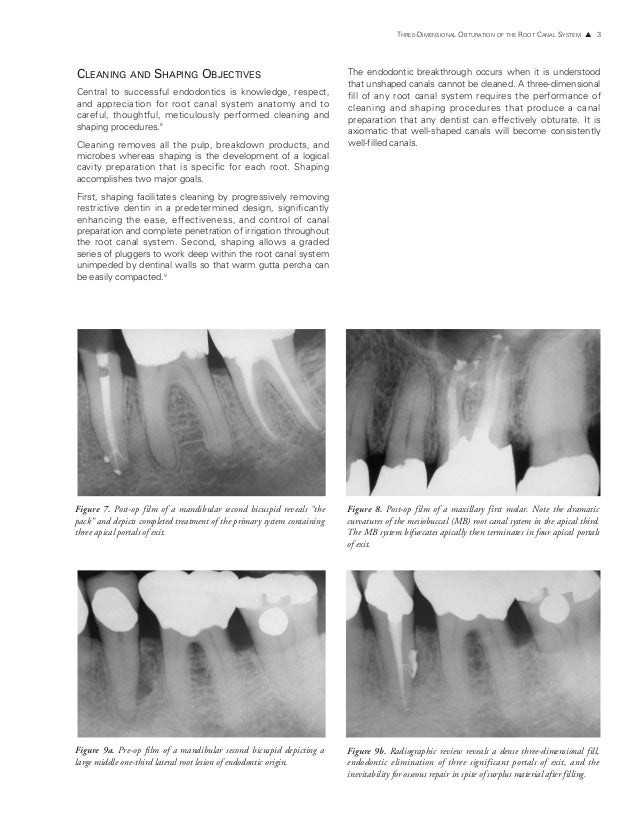

THREEDIMENSIONAL OBTURATION OF THE ROOT CANAL SYSTEM* by Clifford J.…

THREEDIMENSIONAL OBTURATION OF THE ROOT CANAL SYSTEM* by Clifford J.… Root Canal Obturation Systems The filling of root canals, commonly referred to as obturation, is a critical step in successful root canal treatment (rct). The ultimate biologic aim of root canal treatment is the prevention or cure of apical periodontitis. Through this study where we compare two different root canal filling techniques we want to evaluate if one can be considered better than the.. Root Canal Obturation Systems.